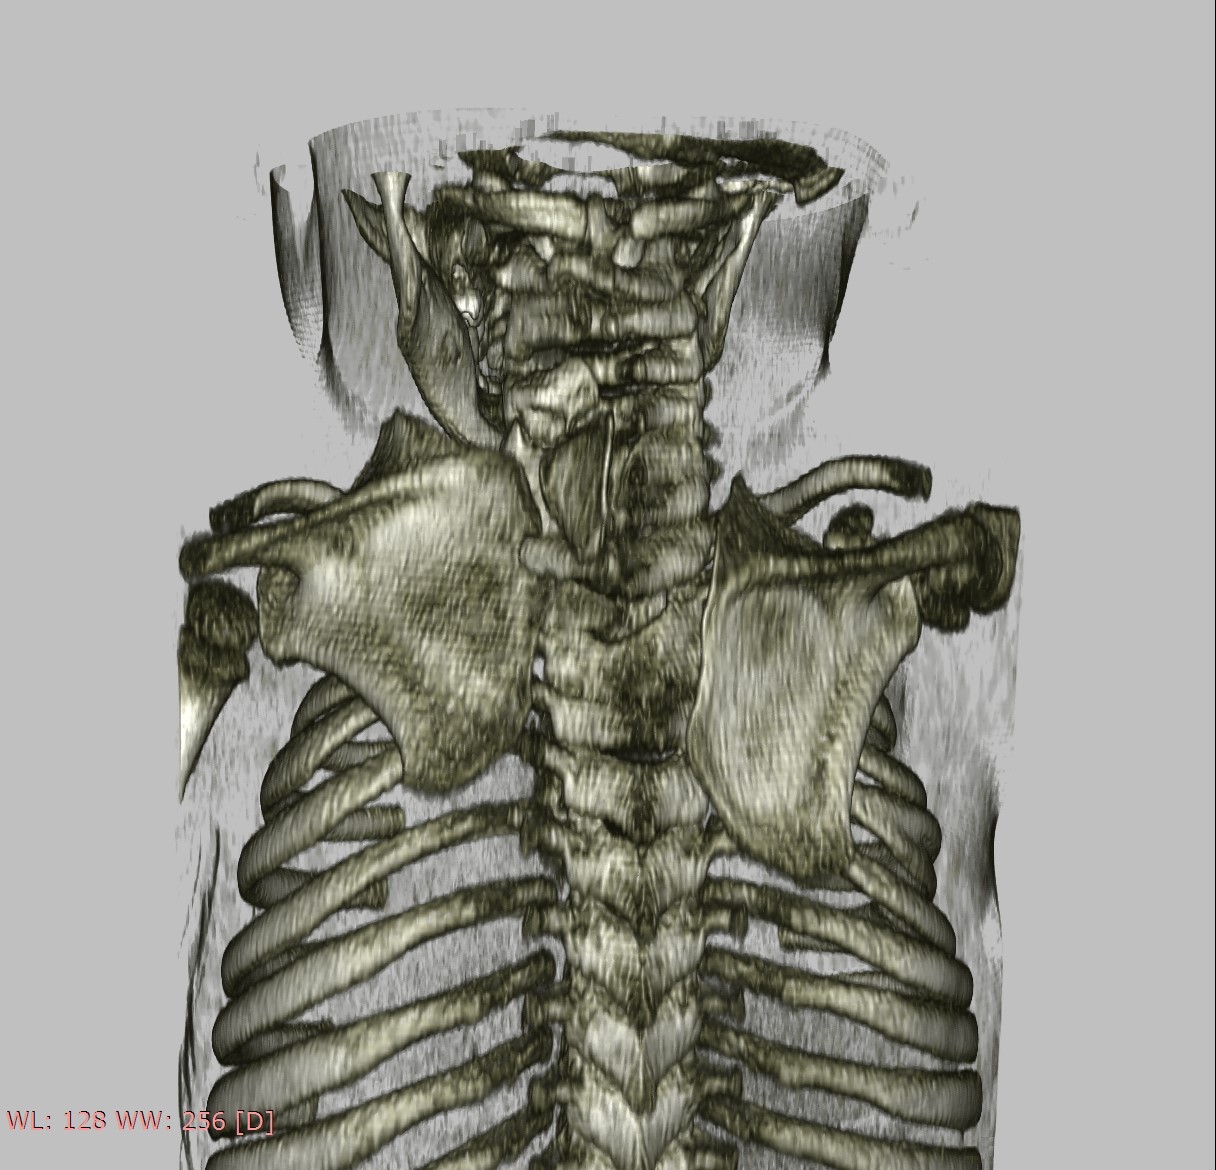

Subsequent radiographs and an ultrasound of both shoulders and scapulae and a close-up X-ray of the left shoulder revealed a fusion of costa 3 and 4. For further evaluation of the cervical spine we made a CT scan which showed a partial fusion of the vertebral corpus C5-C7 on the left and corpus Th2-Th3, Th5-Th6, a fork rib of the 4th rib on the right side (figure 2) and a different morphology of costa 7 on the right. Also seen was a bilateral Sprengel’s deformity; left grade 3 with os omovertebrale, right grade 2 (table 1), articulating with the spinous process C7 (figure 3). As a result of these findings the parents were informed about the diagnoses and the patient will be monitored by a paediatric orthopaedic surgeon until adulthood. Physiotherapy was continued with the aim of maintaining shoulder function. Clinical genetic research revealed no known associated gene mutations, but did show a sequence change in the GDF6 gene with unknown clinical consequences.

Figure 2. 3D reconstruction of CT thorax, cervical spine, shoulders.